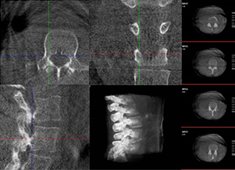

三維重建技術(shù)在醫(yī)學(xué)影像診斷中的應(yīng)用價(jià)值

三維重建技術(shù)在醫(yī)學(xué)影像診斷中的應(yīng)用非常廣泛,主要包括以下幾個(gè)方面:1.診斷疾?。和ㄟ^三維重建技術(shù),醫(yī)生可以更直觀、清晰地觀察到患者體內(nèi)的異常情況,如腫瘤、骨折等,從而更準(zhǔn)確地診斷疾病。...